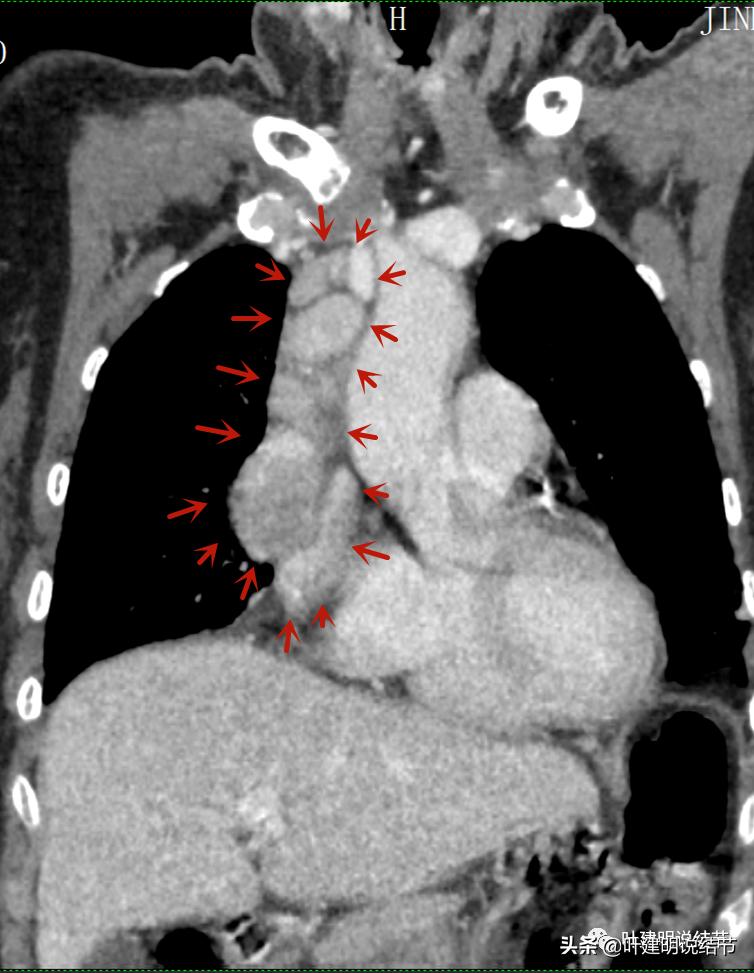

再来看看她的CT增强图像:

以下图片左侧是肺窗,右侧是纵隔窗。红色箭头示病灶,桔色箭头示无名静脉,黄色箭头示支气管,砖色箭头示上腔静脉,蓝色箭头示主动脉,紫色箭头示肺动脉。

病灶胸顶较高位置就出现了,在无名静脉水平

无名静脉略受压

病灶最大横断面水平,在冠状位上显示病灶多个中心似的,从上到下纵隔都有

病灶占据前纵隔从上到下全程,多中心,密度不均,对心脏与大血管有压迫,没有明显侵犯

病灶表面不平,中间有坏死